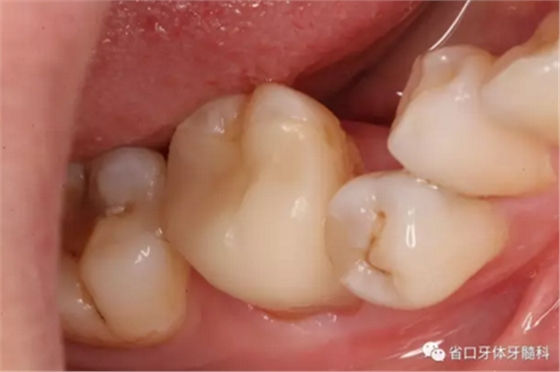

圖9-11 嵌體試戴粘接后,窩溝形態(tài)和、染色有待改進

圖12-14 術后1年回訪:無明顯食物嵌塞,咬合關系良好,牙周健康,未見瘺管

術后隨訪x線片,遠頰、遠舌根尖低密度影消失,近頰根尖低密度影局限(提示近頰根尖瘢痕愈合),嵌體不阻射x線。